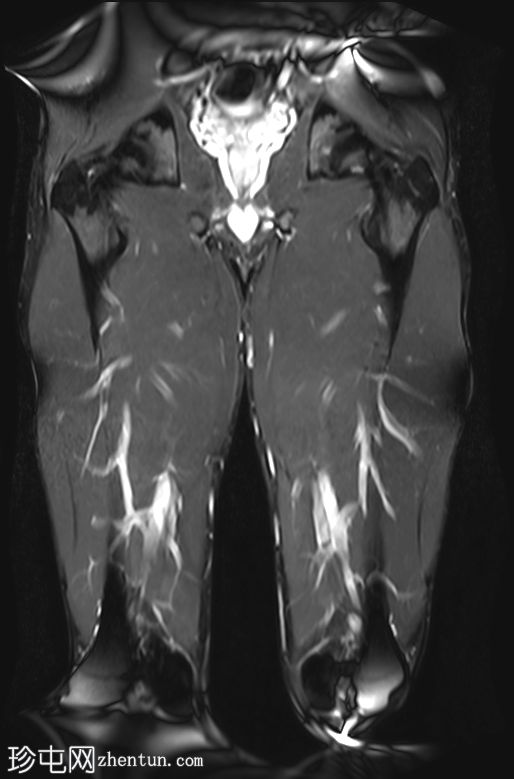

MRI

冠状位

T1 tirm

收肌长肌腱从耻骨起点完全撕脱,可见充满液体的间隙(4毫米),肌腱近端回缩。

相关的肌内水肿累及收肌长肌、短肌和耻骨肌,筋膜间液沿股薄肌向内侧延伸。

MRI 表现与收肌长肌腱从起点撕脱并远端回缩相符,可见充满液体的间隙、筋膜间液和肌肉拉伤。

根据英国田径协会肌肉损伤分类(BAMIC),该损伤被归类为 4c 级。